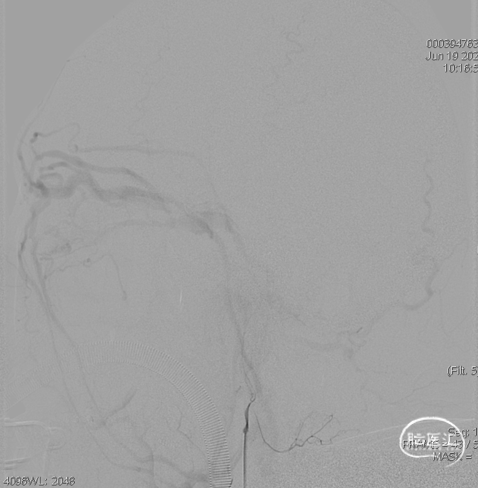

术后造影见瘘口不显影。

术后

术后右侧颈总造影,未见向瘘口供血。

术后铸胶形态及CT下铸胶位置,可见瘘口位于左侧舌下神经管区域。